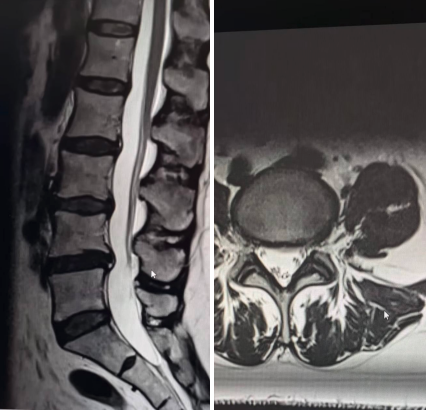

Интересный случай из практики МРТ:

- Женщина 25 лет, сидячая работа, без спорта: на снимке — уже есть протрузии и грыжи, мышцы спины слабо развиты, в них — участки жировой дистрофии. Картина МРТ выглядит «уставшей», несмотря на молодой возраст.